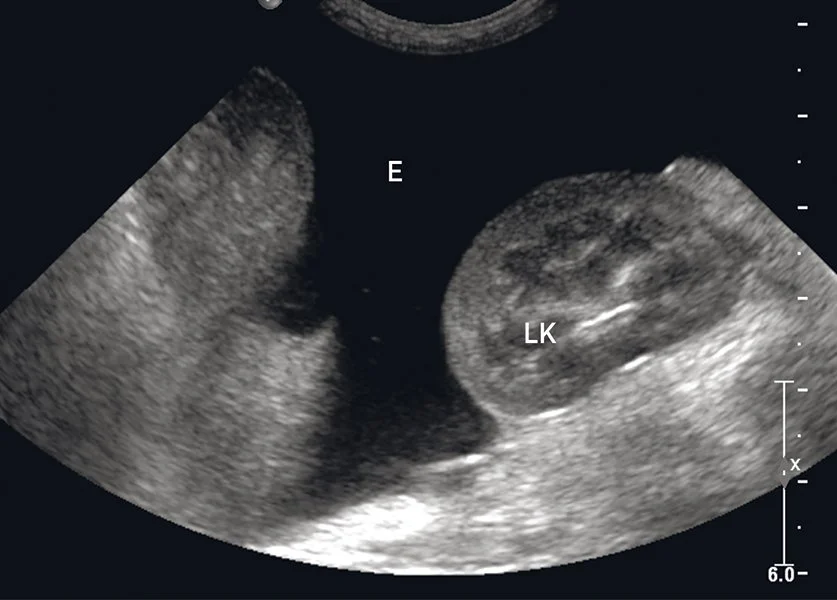

Abdominal fluid next to the left kidney in a dog.

AFAST

Abdominal focused assessment: Primary aim is rapid detection of free abdominal fluid (blood, urine, bile, transudate/exudate). It guides stabilization, sampling (abdominocentesis), and surgical planning. Core windows include diaphragmatico‑hepatic (DH), spleno‑renal (SR), cysto‑colic (CC), and hepato‑renal (HR). Reporting involves binary calls (positive/negative free fluid per window and overall AFAST), fluid scoring (0–4 by window count and pocket size, noting echogenicity/clots), and escalation to the vet with images/clips for action.